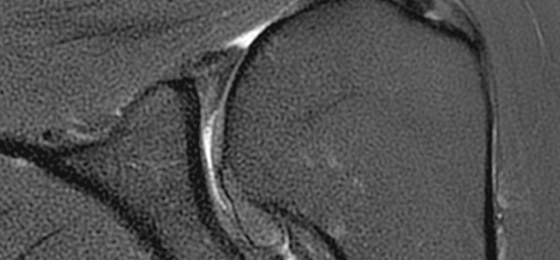

Make no substitutes for image quality

Clearly consistent images

Simply better compared to conventional coil technology.